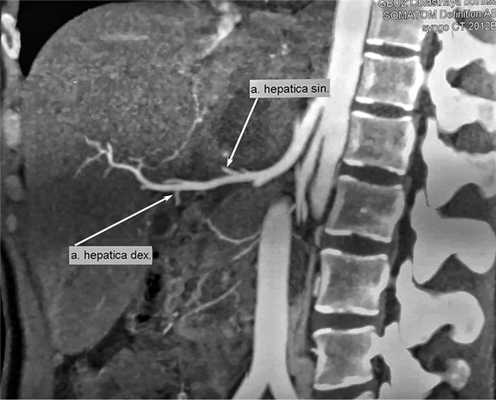

Для определения объема резекции произведена оценка МСК-ангиограмм. В первую очередь интересовала возможность сохранения афферентного и эфферентного кровотока в здоровой части печени. При детальном исследовании правая и срединная печеночные вены по отношению к патологическому образованию интактны, при этом левая печеночная вена полностью вовлечена в патологический процесс (рис. 2). Рис. 2. МСКТ-ангиограмма брюшной полости (артериальная фаза).

В артериальной фазе левая печеночная артерия не визуализируется, правая контрастируется на всем протяжении, с паразитом не контактирует (рис. 3). Рис. 3. МСКТ-ангиограмма брюшной полости (венозная фаза). 1 — патологический очаг в левой доле печени, 2 — фрагмент правой ветви воротной вены, 3 — устье левой ветви воротной вены.